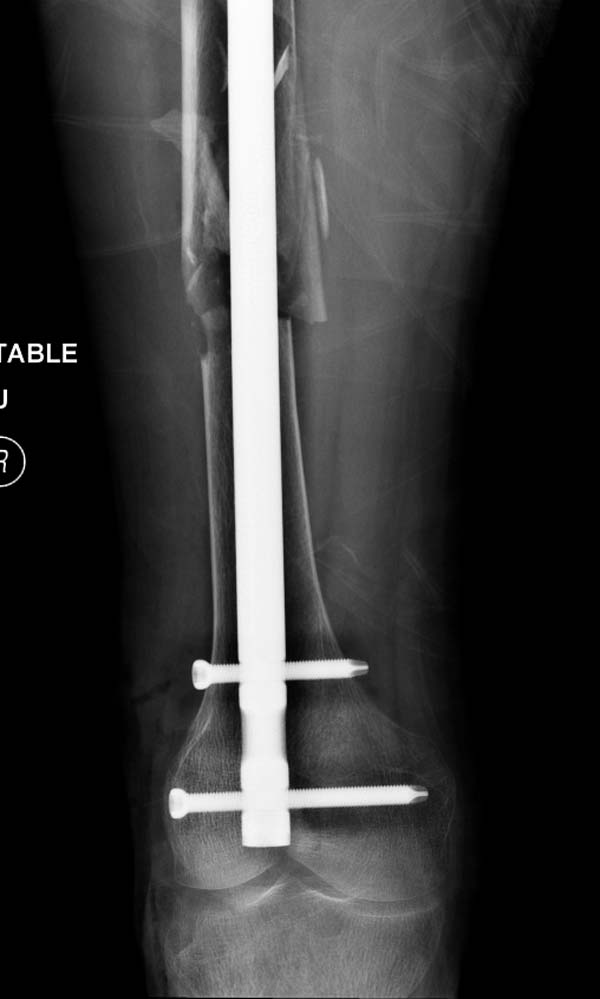

остаться до конца лечения, начал изучать язык... Для облегчения

транспортировки на второй день после поступления правая сторона была

фиксирована ретроградным гвоздем.

Теперь по серьезному. Учитывая качество кости и низкий гемоглобин,

периодический гемодиализ и воодушевленный результатом выступлении

Челнокова, вместо пластины решил попробовать гвоздь. Но жесткие FDА

условии не позволяют воспользоваться дивайсом до получения разрешения на

пользование.

Гвоздь из ретроградного гвоздя DePuy в 15 мм получился немного тоньше,

чем у Российских коллег.

Операция не обошлась без казуса, при подготовке гвоздя произошла ошибка

в расчете. Пришлось коррегигировать по ходу операции, где длинный

дистальный отдел гвоздя срезали во время операции.

А так вроде первый американский опыт прошел удачно. У больного низкий

гемоглобин, который подправили во время операции переливанием крови.

надеюсь, контрагированные мышцы сохранит длину конечности. Контрольный

снимок показал устойчивую фиксацию.